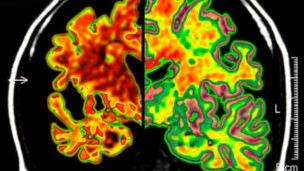

Hablar dos o más idiomas puede proteger a los adultos mayores contra el deterioro cognitivo que conduce a la demencia, señala una nueva investigación.

Hablar dos o más idiomas parece proteger al cerebro de los síntomas de Alzheimer.

Los participantes habían sido sometidos a pruebas cognitivas para medir capacidades como control de atención y memoria y a escáneres cerebrales para medir los cambios cerebrales.